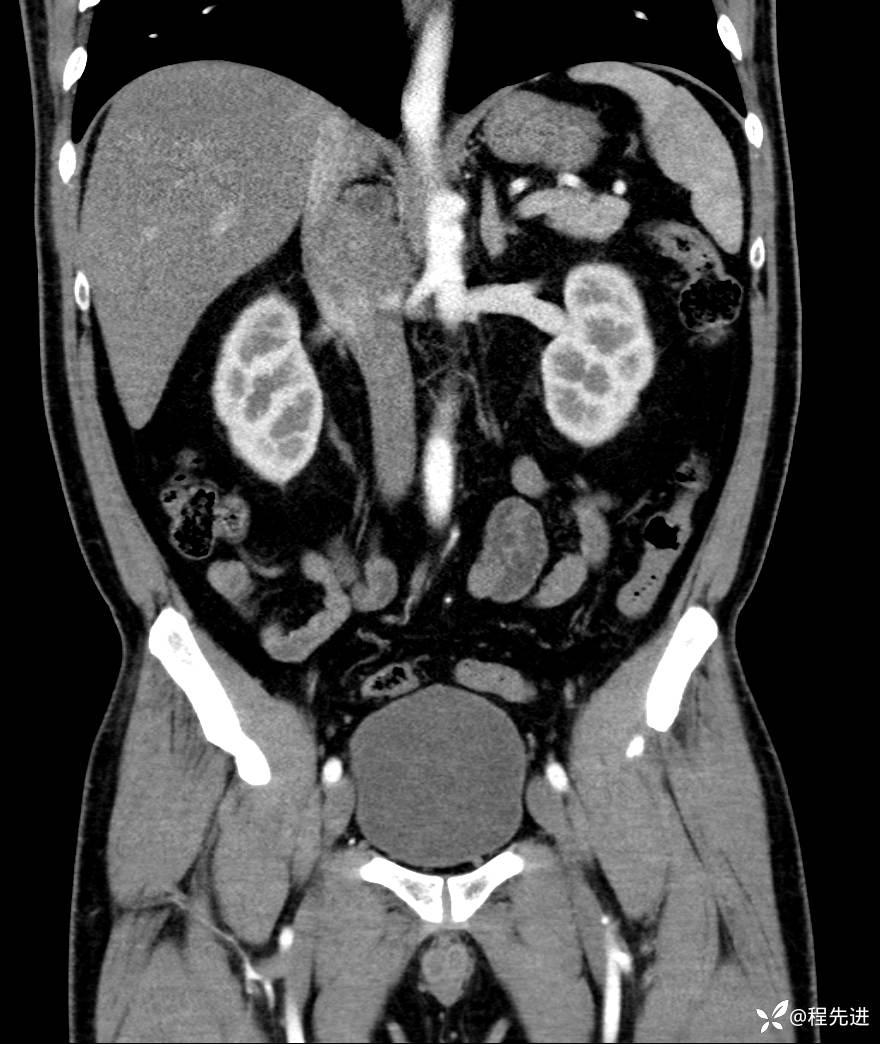

【腹盆】特别精彩病例|发现腹膜后肿物1月余

主诉:发现腹膜后肿物1月余

现病史:患者1月余前查体,行超声检查提示:后腹膜囊实性肿块;慢性胆囊炎伴胆囊内结石;无腹痛腹胀,不伴腹泻发热等;偶感腰背部酸痛。

CT平扫+增强: